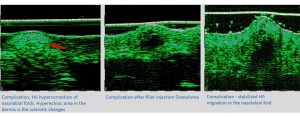

-Έγχυση Πληρωτικών Υλικών (Fillers)

-Lifting με νήματα

-Μέθοδοι θεραπείας υψηλής ενέργειας

(λέιζερ, RF-Ραδιοσυχνότητα, HIFU-Υψηλής Έντασης Εστιασμένος Υπέρηχος, κ.λπ.)